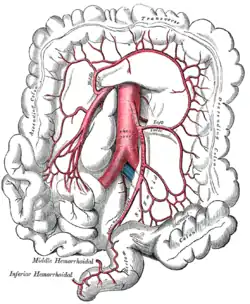

The inferior mesenteric artery and its branches. (Left colic visible at center right.) | |

Sigmoid colon and rectum, showing distribution of branches of inferior mesenteric artery and their anastomoses. (Left colic visible at center left.) | |

The left colic artery is a branch of the inferior mesenteric artery distributed to the descending colon, and left part of the transverse colon. It ends by dividing into an ascending branch and a descending branch;[1] the terminal branches of the two branches go on to form anastomoses with the middle colic artery, and a sigmoid artery (respectively).[2]: 1196

Structure

The left colic artery usually represents the dominant arterial supply to the left colic flexure.[2]: 1196

Course

The left colic artery passes to the left posterior to the peritoneum. After a short but variable course, it divides into an ascending branch and a descending branch.[1]

Branches and anastomoses

Ascending branch

The ascending branch passes superior-ward. It passes anterior to the (ipsilateral) psoas major muscle, gonadal vessels, ureter, and kidney; it passes posterior to the inferior mesenteric vein. Its terminal branches form anastomoses with those of the middle colic artery; it also forms anastomoses with the descending branch (of the left colic artery).[2]: 1196

Descending branch

The descending branch passes inferolaterally.[2]: 1196 It forms anastomoses with the superior-most sigmoid artery[1] as well as the ascending branch (of the left colic artery), thereby participating in the formation of the marginal artery of the colon.[2]: 1196